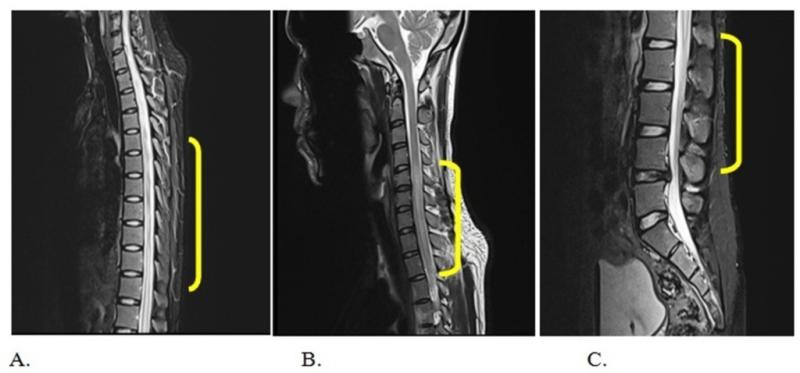

Transverse myelitis (TM) is a rare neurological disorder caused by inflammation of the spinal cord, often associated with autoimmune, infectious, or post-vaccination etiologies. It manifests as sensory, motor, or autonomic dysfunction and may lead to partial or complete paralysis if not treated promptly.

Rising prevalence of autoimmune diseases such as multiple sclerosis (MS) and NMOSD has boosted early detection and intervention. The market has evolved from conventional corticosteroid therapy toward integrated care involving immunoglobulin infusions, plasma exchange, and biologic immunomodulators. Advancements in MRI-based imaging and biomarker-based diagnosis are further improving patient outcomes.